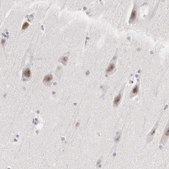

All Prestige Antibodies Powered by Atlas Antibodies are developed and validated by the Human Protein Atlas (HPA) project and as a result, are supported by the most extensive characterization in the industry.

The Human Protein Atlas project can be subdivided into three efforts: Human Tissue Atlas, Cancer Atlas, and Human Cell Atlas. The antibodies that have been generated in support of the Tissue and Cancer Atlas projects have been tested by immunohistochemistry against hundreds of normal and disease tissues and through the recent efforts of the Human Cell Atlas project, many have been characterized by immunofluorescence to map the human proteome not only at the tissue level but now at the subcellular level. These images and the collection of this vast data set can be viewed on the Human Protein Atlas (HPA) site by clicking on the Image Gallery link. We also provide Prestige Antibodies® protocols and other useful information.

• IHC tissue array of 44 normal human tissues and 20 of the most common cancer type tissues.